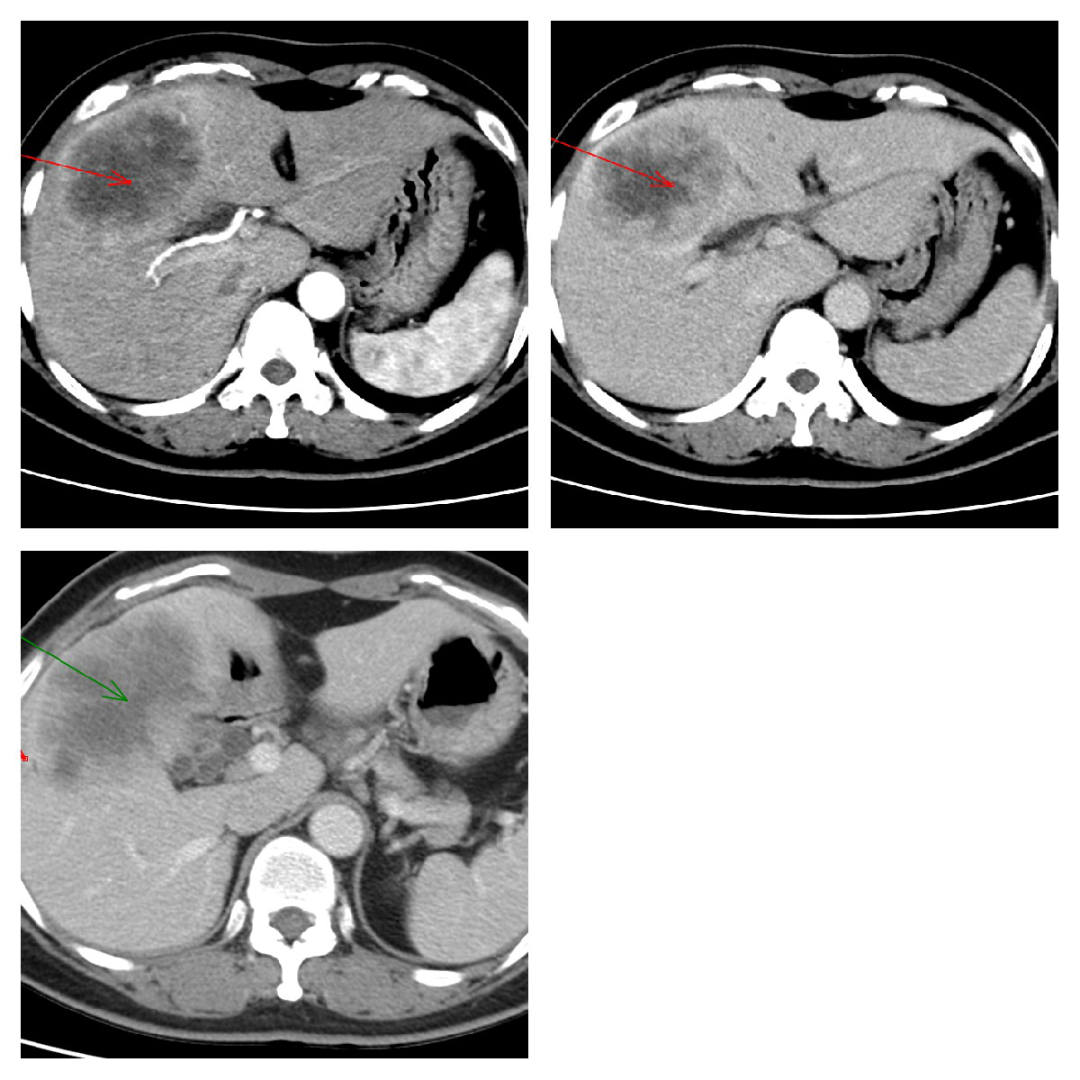

肝细胞肝癌:平扫呈低密度灶,动脉期快速强化,静脉期造影剂快速退出,延迟期可见假包膜。

肝内胆管细胞癌:动脉期不规则环形强化,边界不清;静脉期及延迟期造影剂缓慢向肿瘤中心渐入的「延迟强化」。